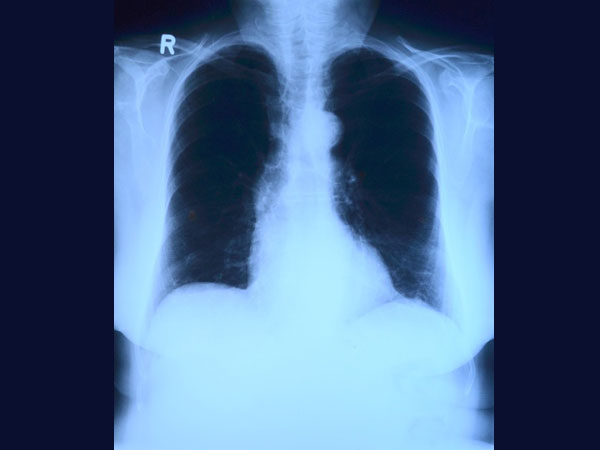

Chest

X-rays:

One

of

the

easiest

and

simplest

methods

to

diagnose

asthma

is

take

a

x-ray.

This

can

be

done

for

children

as

well

adults.

above

five

years,

X-ray

an

easy

reliable

diagnostic

method

detecting

asthma.